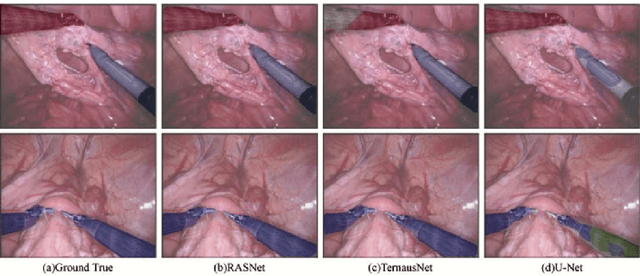

Abstract:Segmentation for tracking surgical instruments plays an important role in robot-assisted surgery. Segmentation of surgical instruments contributes to capturing accurate spatial information for tracking. In this paper, a novel network, Refined Attention Segmentation Network, is proposed to simultaneously segment surgical instruments and identify their categories. The U-shape network which is popular in segmentation is used. Different from previous work, an attention module is adopted to help the network focus on key regions, which can improve the segmentation accuracy. To solve the class imbalance problem, the weighted sum of the cross entropy loss and the logarithm of the Jaccard index is used as loss function. Furthermore, transfer learning is adopted in our network. The encoder is pre-trained on ImageNet. The dataset from the MICCAI EndoVis Challenge 2017 is used to evaluate our network. Based on this dataset, our network achieves state-of-the-art performance 94.65% mean Dice and 90.33% mean IOU.